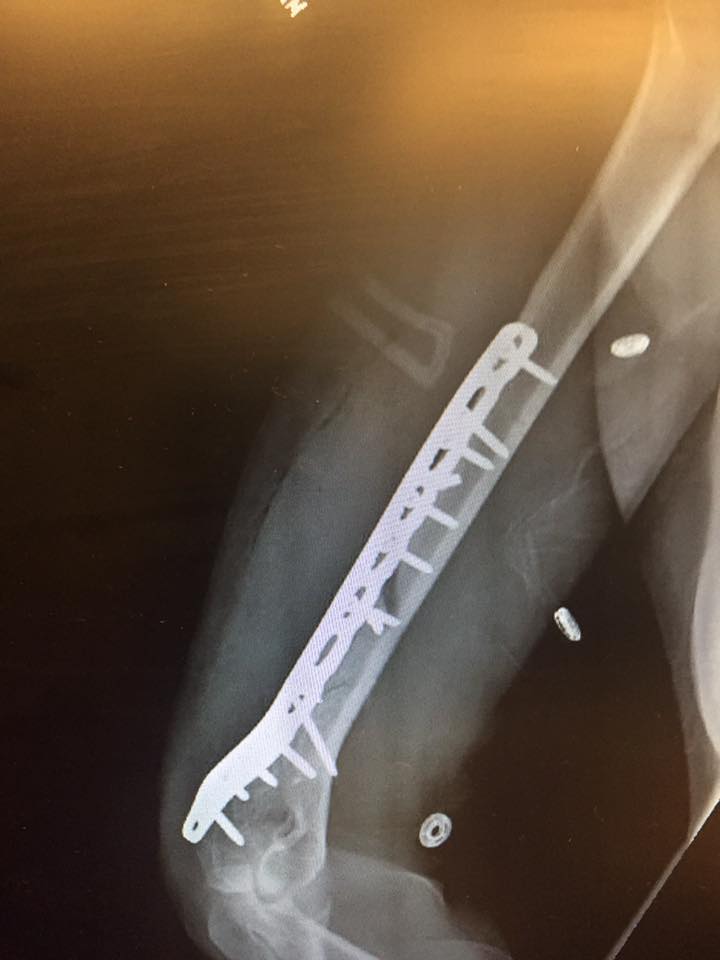

Ad annunciare la caduta e lo stop a causa della rottura del braccio è la stessa campionessa Usa, che su Facebook ha pubblicato uno status corredato con le radiografie che mostrano le fratture sul suo braccio:

“Sfortunatamente, ieri sono caduta mentre mi stavo allenando a Copper e ho riportato una grave frattura dell’osso omero del mio braccio destro. Sono stata operata la scorsa notte a Vail con successo e tutti si sono presi cura di me alla grande.